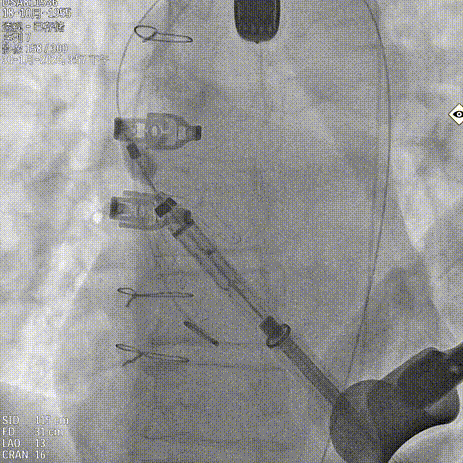

释放瓣膜

锁丝脱钩

撤出输送器

25球囊后扩

术后造影 反流消失